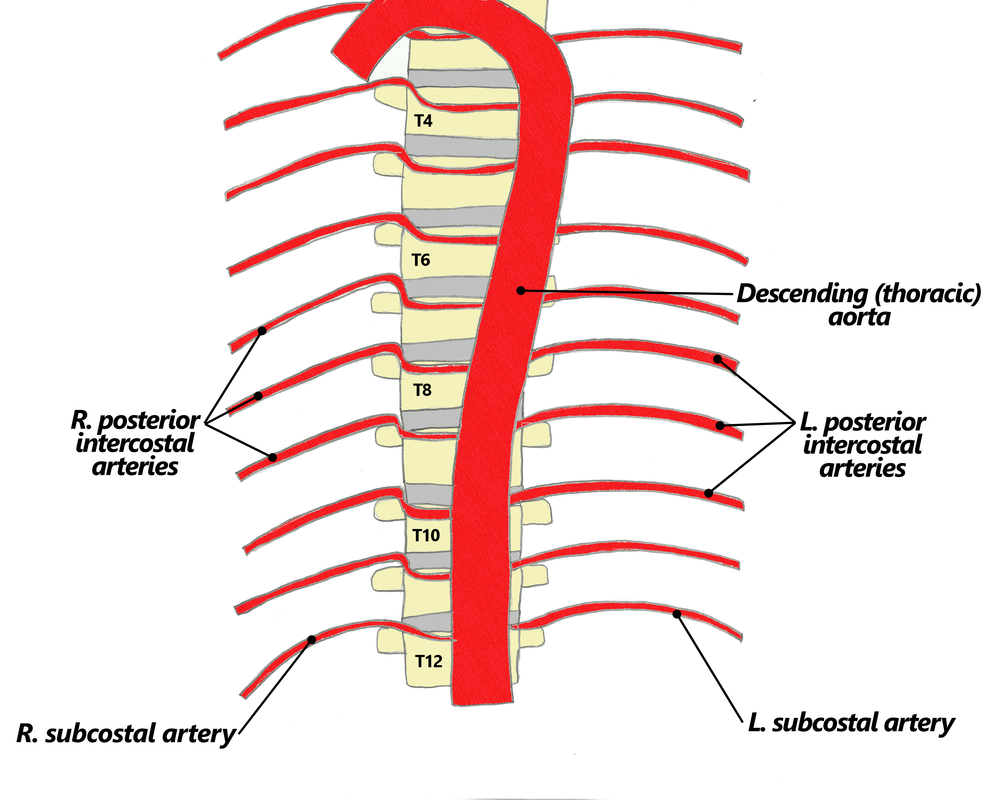

- Blood supply to the rib cage originates from what 2 places?

- what 2 arteries supply the intercostal spaces of the rib cage

aorta and subclavian artery

Anterior and posterior intercostal arteries

notice how branches from the aorta go around and supply the rib cage

go back and rememeber the subclavian artery and how it had the VA, the thyrocervical trun and the costocervical trunk.....one branch from the costcervical trunk that went up to the skull was the deep cervical artery....what is the branch of this trunk that goes down?

what then branches from the artery?

the supreme intercostal artery

the 1st and 2nd posterior intercostal arteries

notice the subclavian, the costcervical trunk and the deep cervical artery and the supreme intercostal artery...then notice how it splits off into 2 branches under the clavicle

the 3rd through the 11th intercostal arteries branch off from what?

notice it in the picture?

from the aorta

Posterior intercostal arteries:

- There are only 11 “posterior intercostal arteries” that supply what?

- The ________ which arises from aorta helps supply what as it runs inferior to the rib?

the 11 intercostal spaces

subcostal artery

the 12th rib

notice how in the picture you can see the subcostal artery down below the ribs as it branches from the aorta

notice how the intercostal arteries run superior and inferior in the intercostal spaces

look at all the arteries and their relationship

look at how the posterior intercostal arteries come from the back and wrap around the intercostal spaces from the back